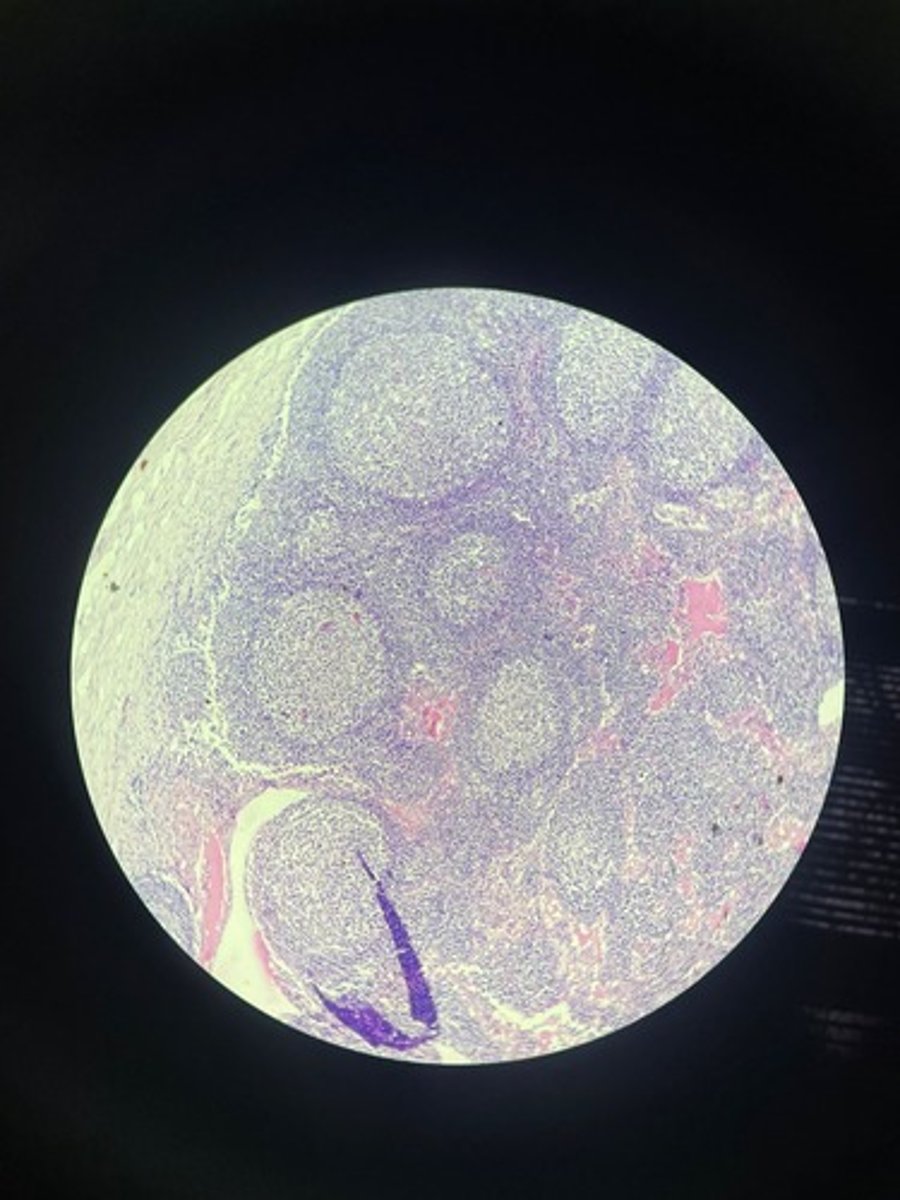

Spleen HE

Spleen HE

Spleen HE